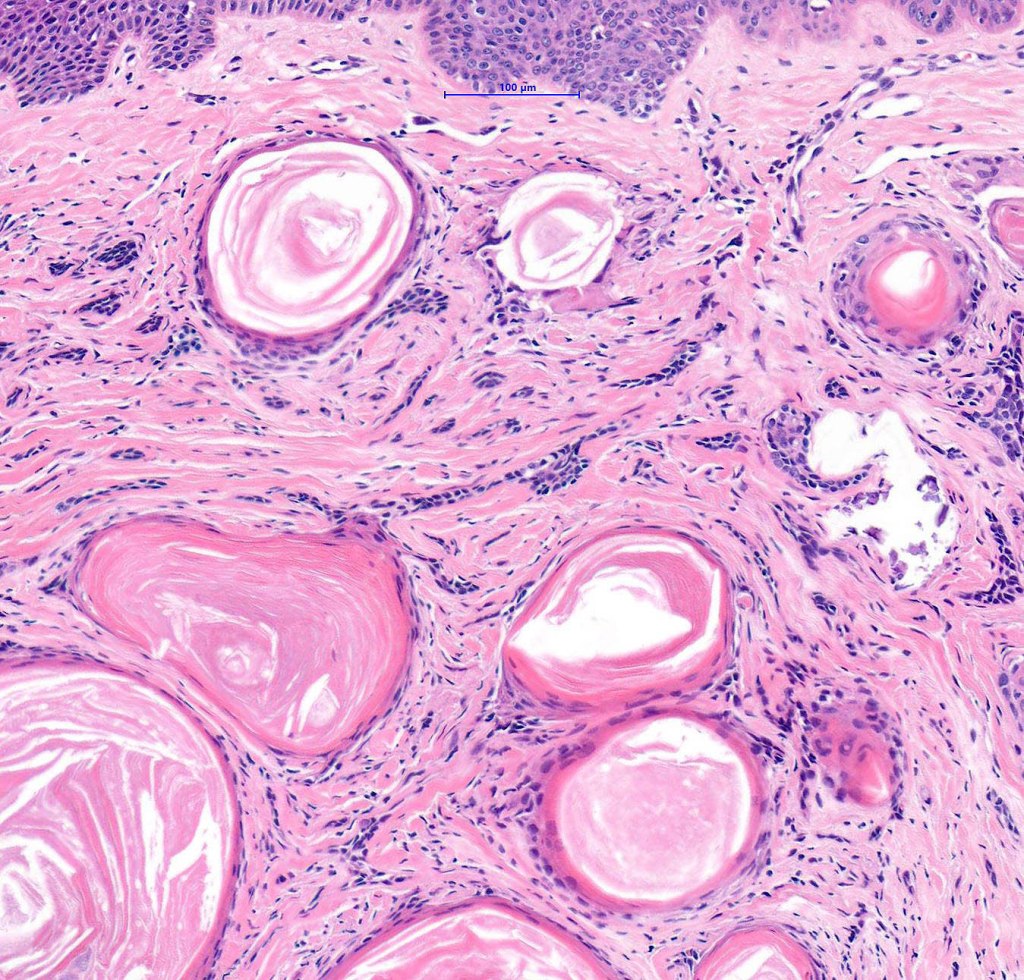

Histological features

•Consists of narrow epithelial strands & keratocysts embedded in a dense stroma

•Generally involves superficial & mid dermis but does not extend into the subcutaneous fat

•No evidence of glandular differentiation

•Calcification, foreign body giant cell reaction to keratin & bone are inconstant findings

•Epithelial stands may arise from follicular epithelium

•Can rarely see matricial differentiation